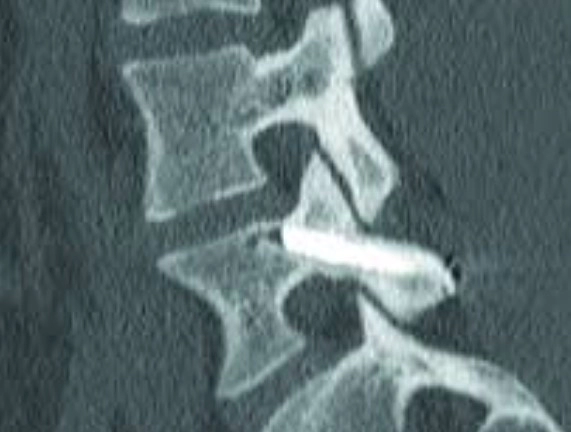

척추분리증은 척추의 일부가 분리되거나 약해지는 상태를 말합니다. 이 조건은 보통 척추의 추궁의 특정부분이 결손되거나 분리되는 데 관련되며, 이는 척추를 안정시키는 데 중요한 구조물입니다. 이것은 가장 흔하게는 척추의 하부인 요추 부분에서 발생합니다.